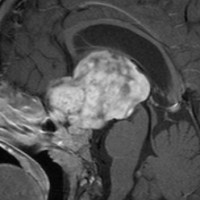

頭蓋内単視神経膠腫

2歳のとき右眼の失明で発症し化学療法が継続されました。これは8歳の時の視野検査です。数ヶ月の経過で左眼も耳側半盲となりました。手術前の視野検査で,この腫瘍が右視神経から発生し,左眼は腫瘍に侵されず,たんに圧迫を受けていることがわかります。ですから,単視神経膠腫です。

化学療法を長く受けた腫瘍は巨大でした。この腫瘍を亜全摘出しました。幸い左眼の視野は改善して視床下部下垂体障害もでませんでした。2歳の時に開頭手術で全摘出するべきものでした。